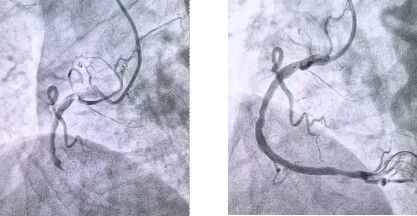

患者抵達(dá)醫(yī)院后,簡(jiǎn)化掛號(hào)、繳費(fèi)等中間環(huán)節(jié),迅速溝通病情,需要緊急介入治療,獲得家屬同意,立即送至導(dǎo)管室。造影顯示其右冠狀動(dòng)脈中段完全閉塞,醫(yī)生迅速實(shí)施血栓抽吸,球囊擴(kuò)張和藥物洗脫支架植入術(shù)。36 分鐘后,閉塞血管恢復(fù)正常血流,吳大爺?shù)难獕?、心率逐漸平穩(wěn),胸痛癥狀明顯緩解。術(shù)后三天,他便轉(zhuǎn)入普通病房進(jìn)行康復(fù)訓(xùn)練,重拾健康生活。